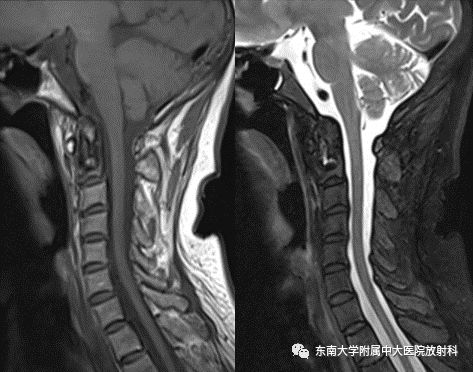

颈椎病是指颈椎间盘退行性变及其继发性病理改变所引起的一系列症状和体征。颈椎病常见于长期从事低头工作的人群,如办公室工作人员、司机等。颈椎病的症状包括颈肩部疼痛、手臂麻木、头晕、头痛等。治疗颈椎病的方法包括药物治疗、物理治疗、按摩和手术治疗。